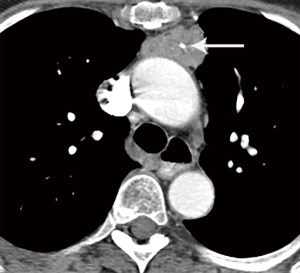

Computed tomography (CT) with contrast is the imaging modality of choice to evaluate thymic tumors due to its high spatial and temporal resolution, ease of access, and convenience. CT can reliably discern location, size/shape, morphology, margins, density, enhancement, and relationship to, or invasion of, adjacent structures (4) (Figure 2). Overall, CT is equal or superior to magnetic resonance imaging (MRI) in the evaluation of mediastinal masses with the caveat that MRI better evaluates thymic cysts or cystic components of tumors (5) (Figure 3).

The role of fluorodeoxyglucose (FDG) positron emission tomography (PET)/computed tomography (CT) in thymic mass evaluation is incompletely defined. False-positive studies can be seen with FDG uptake in non-neoplastic masses, such as in the setting of infection, thymic hyperplasia, or fibrosing mediastinitis. False-negative studies can be seen in certain histological types of thymic malignancy with lower metabolic activity. Additionally, there is lack of technique standardization which results in quantitative variability between studies (8). Given that other prevascular masses such as malignant germ cell tumor and lymphoma are often FDG avid, the presence of a hypermetabolic prevascular mass cannot distinguish between various tumors. There are studies that report that FDG uptake can help predict tumor invasiveness and prognosis. Other studies report FDG uptake as useful in differentiating low-grade from high-grade thymic malignancies; however, other studies report these observations as controversial due to overlapping imaging findings and FDG uptake between low-grade and high-grade thymic tumors (9). Overlapping findings are less common in more aggressive tumors, such as thymic carcinoma, due to higher overall tumor metabolism, with studies reporting that a maximum standard uptake value (SUVmax) of 6 can serve as a cutoff between thymic carcinoma and lower grade thymic tumors (10) (Figures 2,3). However, this threshold cannot differentiate thymic carcinoma from other malignancies such as lymphoma or non-seminomatous germ cell tumor. Finally, PET/CT clearly has a role to detect occult metastasis in hypermetabolic tumors.

Thymoma typically presents as a smooth or lobular mass involving one lobe of the thymus, although bilateral involvement can occur (39). Most thymomas demonstrate homogeneous enhancement, although, approximately one third can be heterogeneous due to areas of hemorrhage, necrosis, cystic change, or calcification (1) (Figures 8,9). Imaging characteristics can vary according to WHO histological classification, with vascular invasion and pleural/pericardial involvement more common with more aggressive histology (Figure 2). The thymomas with the more aggressive histologies tend to be larger, more lobular or irregular, have cystic or necrotic change, areas of calcification, or evidence of infiltration into surrounding fat (40-42) (Figure 10).

The role of FDG PET/CT in thymoma imaging is limited. Given the presence of FDG uptake in the normal and hyperplastic thymus, especially in younger adults and children, false-positive results can occur. In fact, physiologic uptake has been reported in 28% of patients under 40 years of age and up to 73% in children less than 13 years of age (44). PET/CT has not been shown to differentiate different WHO histological classifications of thymic tumors, although the more aggressive histologies tend towards higher FDG uptake (45,46) (Figures 2,3). Indium111 octreotide nuclear medicine scans have now been replaced by 68Ga-labeled somatostatin analogues because 68Ga-labeled somatostatin analogues, such as 68Ga-DOTATATE, are used for PET/CT, and thus provide better resolution.

Thymic carcinoma and thymic neuroendocrine tumors have similar imaging characteristics which may often overlap with the more aggressive histologies of thymoma, such as B3 thymoma. Thymic carcinomas and neuroendocrine tumors commonly present as large prevascular masses with irregular or poorly marginated borders, areas of necrosis or cystic change, and hemorrhage. Compared with thymomas, there is a greater incidence of local invasion (1) (Figures 2,11). Pleural or pericardial nodules, pleural effusion, and distant metastasis are more commonly seen with thymic carcinoma or thymic neuroendocrine tumor than thymoma (Figure 12). More aggressive thymic epithelial tumors can invade or compress the SVC resulting in SVC syndrome. This is a clinical syndrome marked by swelling of the neck, face, and upper extremities, with associated cough, headache, and shortness of breath. Pleural metastatic disease, which is more common in thymic carcinoma and thymic neuroendocrine carcinoma, generally consists of small enhancing pleural nodules or areas of enhancing pleural thickening. These are generally adequately assessed with thin-slice contrast-enhanced CT, although, contrast-enhanced MRI and PET/CT can be of additional benefit in questionable cases.